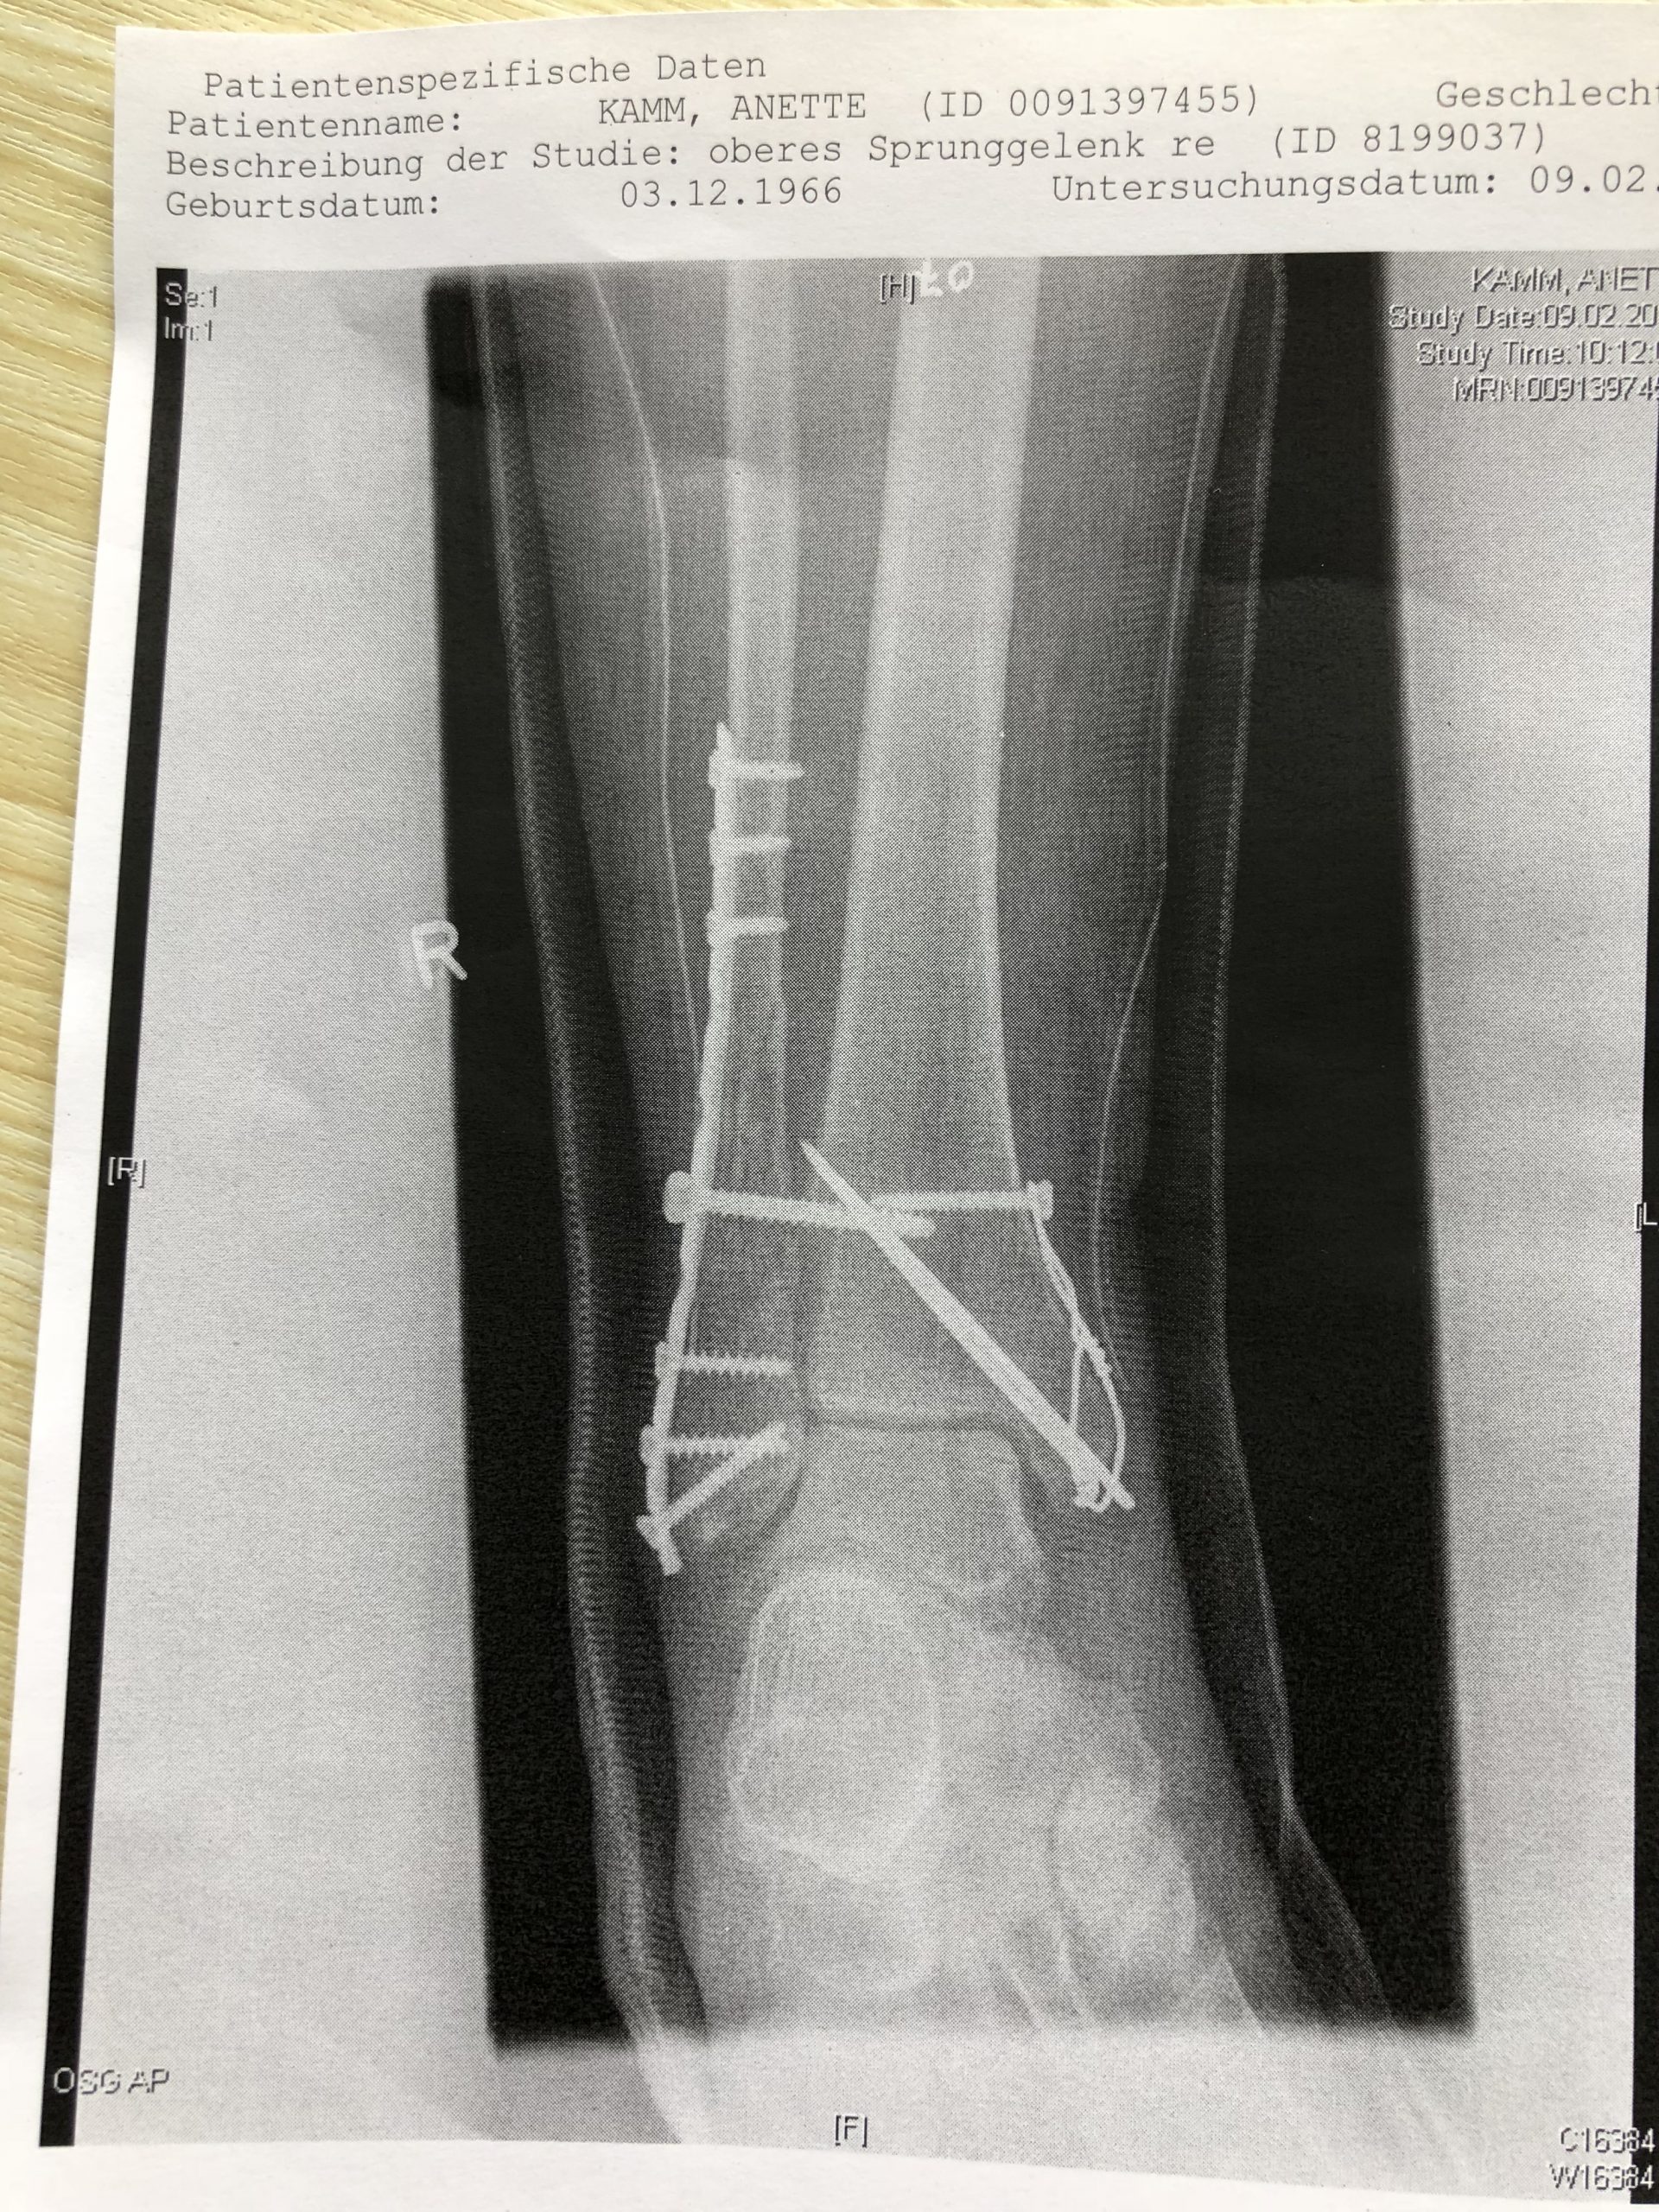

Für die Orthopäden unter uns gibt es noch mehr Details zu diesem besonderen Fall

Drähte, Leisten und Schrauben ... was man in so ein Bein alles einbauen kann, damit es wieder richtig zusammen wächst